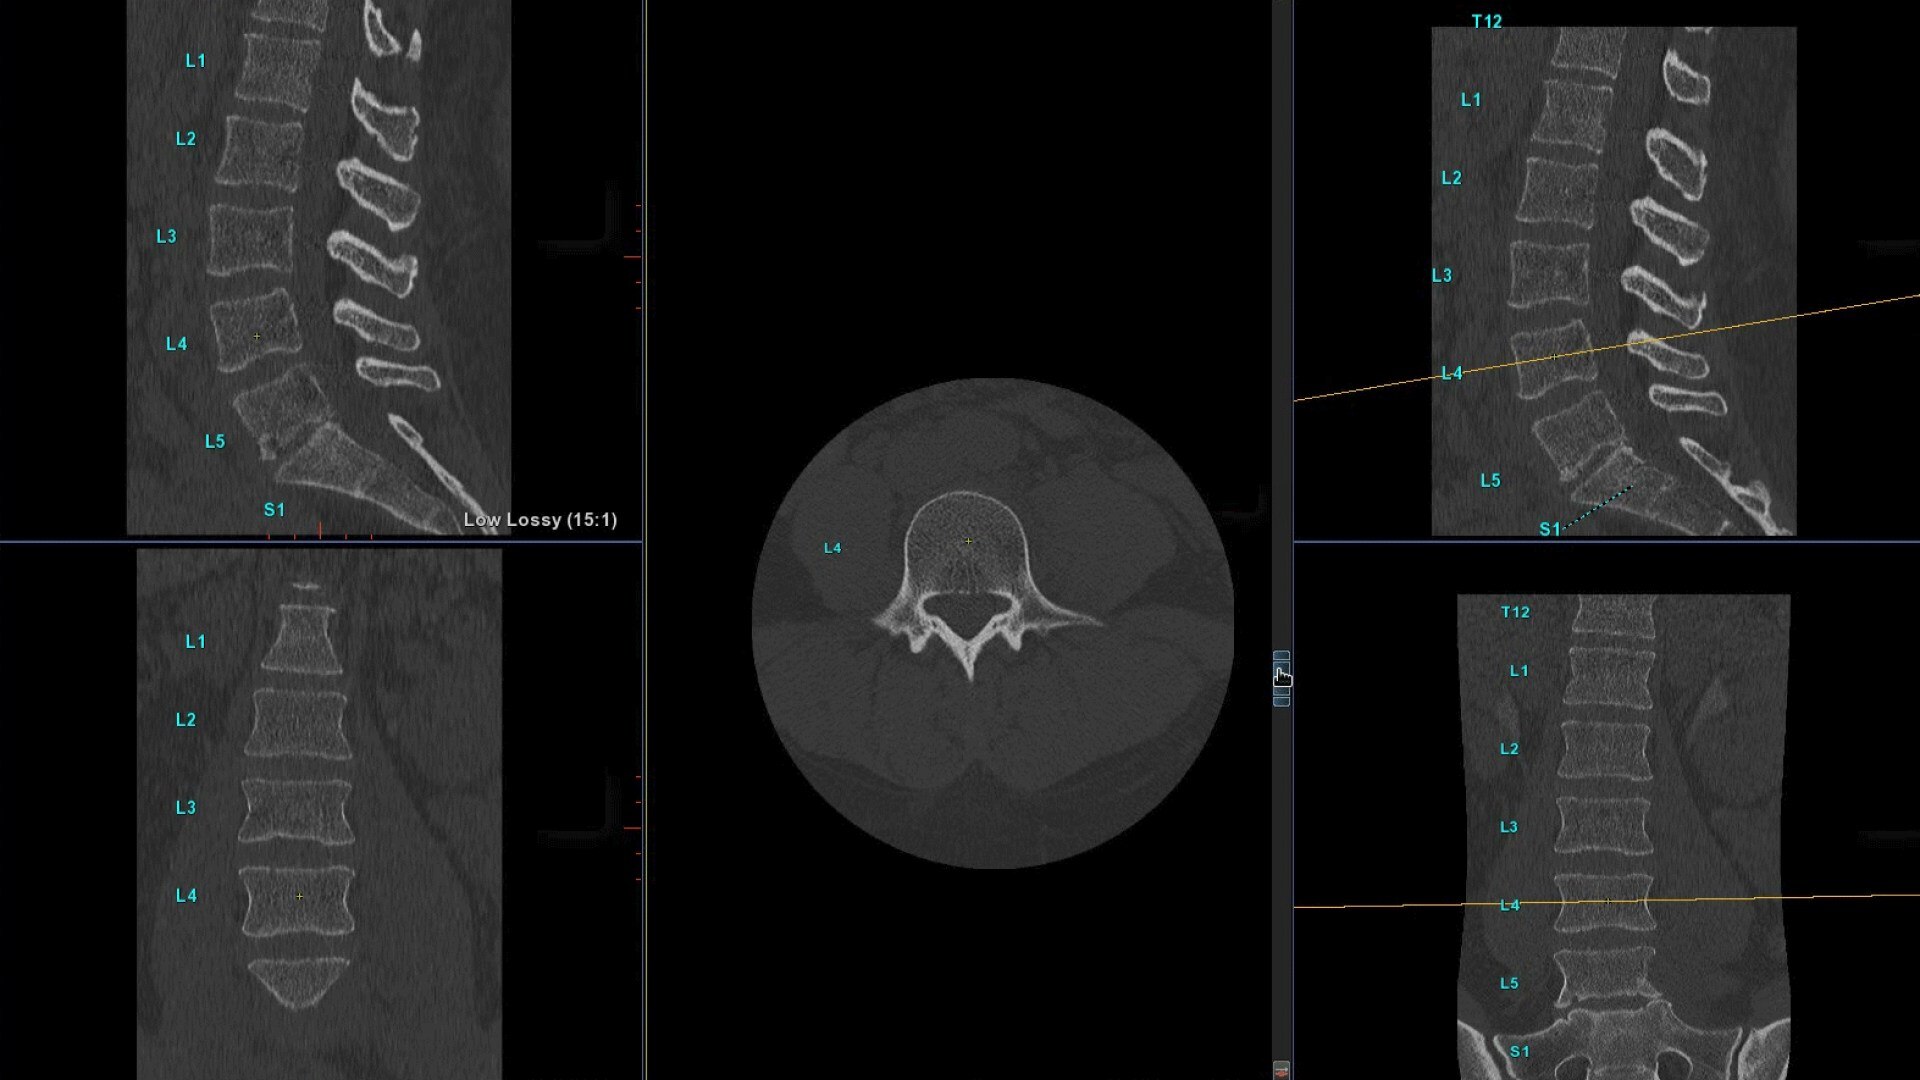

Le immagini incluse in questo documento sono esempi rappresentativi e possono variare in base alle configurazioni.